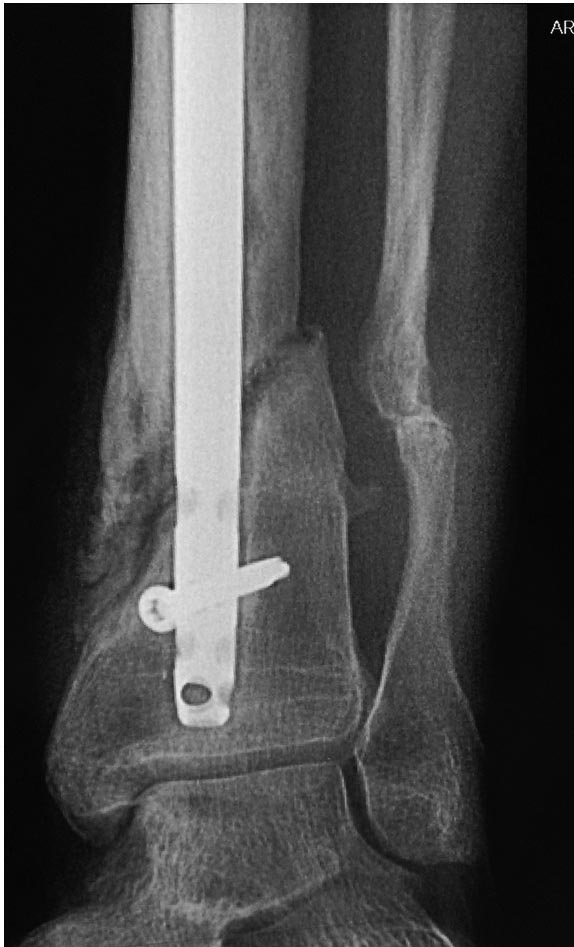

Уважаемые коллеги выразите Ваше мнение по следующему случаю. Молодой

человек, 27 лет, находится на лечении с диагнозом: Ложный сустав

большеберцовой кости в нижней трети, фиксированный интрамедуллярным

блокированным стержнем (12.02.2014 г), ложный сустав малоберцовой кости

в нижней трети левой голени, посттравматический артроз левого

голеностопного сустава 1 стадии. Укорочение левой нижней конечности на

В феврале 2014 г выполнил первым этапом: Фиксацию ложного

сустава в АНФ с восстановлением осей сегментов. Через семь дней БИОС с

рассверливанием.

После операции - вальгус голеностопного сустава. Гладкое течение

послеоперационного периода. Нагрузка по переносимости боли. Через 6

недель динамизация, через 2 недели стали мигрировать 2 фронтальных

винта. Пытался подкрутить, пришлось удалить.